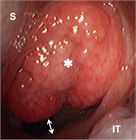

1. 扁桃肥大(アデノイド肥大を含む)は小児の睡眠時無呼吸(obstructive sleep apnea:OSA)を含む閉塞性睡眠時呼吸障害(obstructive sleep-disordered breathing:oSDB)の最も一般的な原因であり、このような小児患者に口蓋扁桃摘出術 ± アデノイド切除術は非常に有効である。一方、扁桃肥大は成長とともに軽減すること、術後出血などの術後合併症もみられることから、手術適応は慎重に評価しなければならない。成人の扁桃肥大では腫瘍性病変の可能性を念頭に置いて診断を進める必要がある。